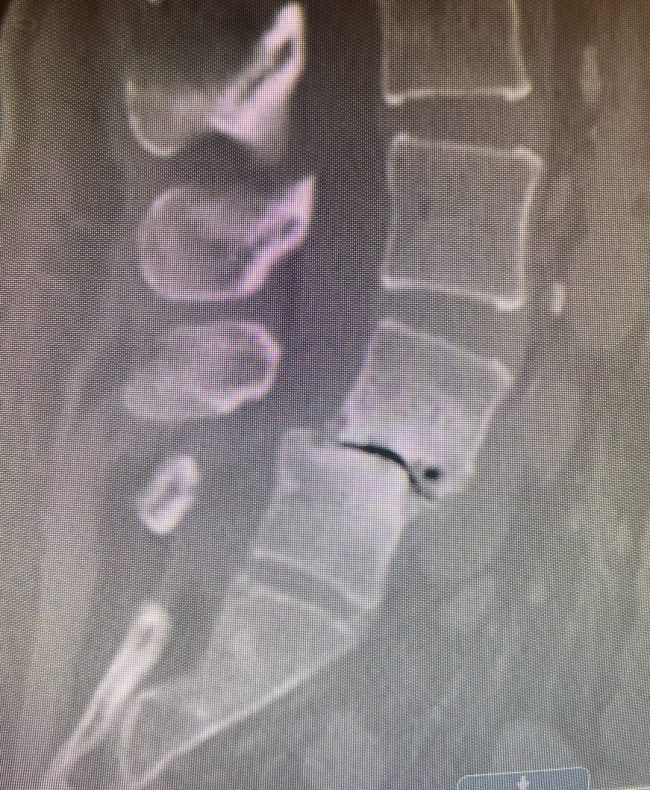

Comprehensive Anterior–Posterior Fusion Restores Alignment and Function for L4–5 Deformity

👉 Spinal deformities / Anterior-posterior (front-back) Spinal Fusion — At Texas NeuroSpine Surgery, our goal is to always find the least invasive approaches for the best surgical outcome. However, some cases require more extensive approaches, as in this case of an L4-5 deformity in a patient with rheumatoid arthritis and years of debilitating low back…